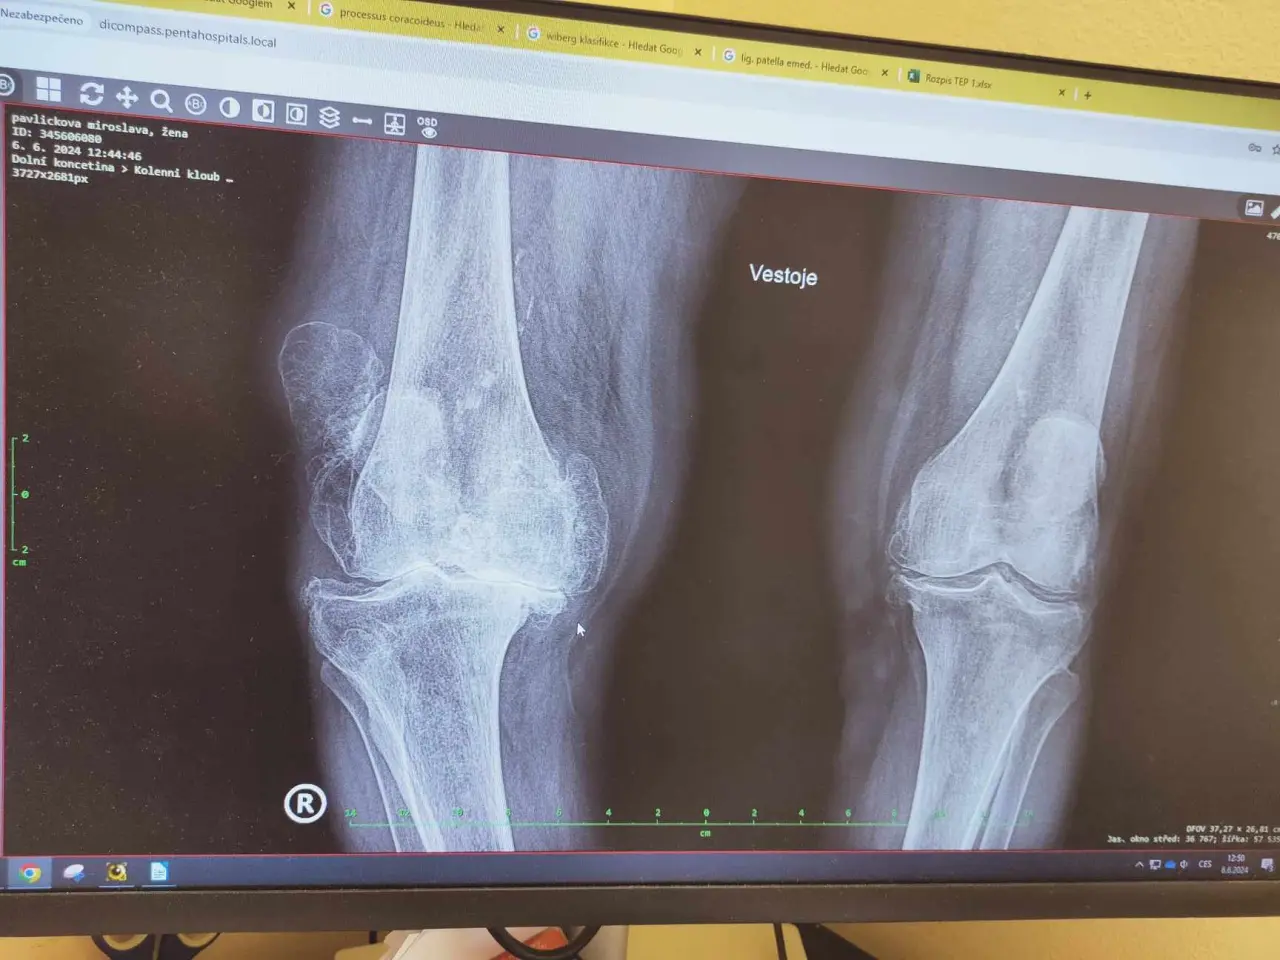

Sbírka pomůže invalidní babičce, která po těžkém úraze s trvalou deformací nohy ztratila schopnost samostatné chůze. Její stav je kombinací těžkého zranění + věku, které už nelze řešit operací (právě kvůli pokročilému věku).

Pomoc bude směřovat na zajištění mobility více než 90leté babičky, která se po těžkém úraze a neúspěšné léčbě, v kombinaci s velmi vysokým stářím stala již zcela imobilní. V reálu je její koleno 2,5× větší než druhé (RTG snímek nezachytí) stav je už nezvratitelný, doživotní.